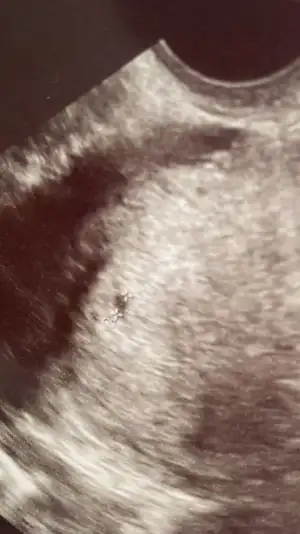

Yok sezeryan. Bebek 2 haftadır kilo almıyor bir de bağırsakta çok kaka gördü korktu. Ve alttan muayenemde hiç açılma yumuşama görmedi. Geleceği yok gibi bir de kilo da almıyor kaka riski de olunca almak istedi ben de doktoruma güvendimHadi hayırla inşallah,suni sancı mı verecekler canım